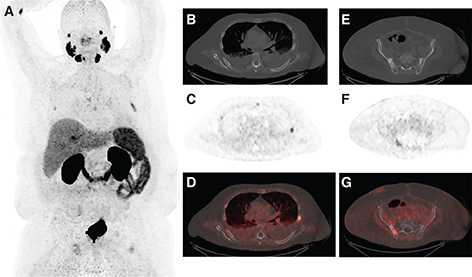

Recently, two PSMA-targeting molecular imaging agents Gallium-68 prostate specific membrane antigen (68Ga-PSMA-11) and fluorine-18 piflufolastat (18F-DCFPYL) received FDA approval after the completion of two landmark clinical trials, VISION and TheraP, which evaluated their safety and efficacy in treating metastatic castrate-resistant prostate cancer. These two agents have superior sensitivity and specificity profiles for recurrent or metastatic prostate cancer than the earlier approved PET molecular imaging agents (i.e., 18F-fluciclovine [Axumin] and 11C-choline). PSMA-targeting diagnostic imaging is critical in identifying eligible patients who can benefit from 177Lu-PSMA therapy (Figure 1) and serves as a diagnostic component in 177Lu- PSMA theranostics. At present, there is no definitive consensus on what amount of PSMA uptake in a metastatic lesion is considered sufficient for a patient to derive significant benefit from 177Lu-PSMA therapy. Following the example of neuroendocrine tumor theranostics, adequate uptake is generally considered when most metastatic lesions show uptake higher than that of normal organs such as the liver. For example, the inclusion criteria of the TheraP phase 2 trial of 177Lu-PSMA-617 required SUVmax values at dominant sites of metastatic disease to be least 1.5 times the SUVmean value of the liver on baseline 68Ga-PSMA-11 PET imaging and excluded patients with FDG-avid metastatic lesions that lacked PSMA expression (16).

Fig 1

Figure 1. An 89-year-old male with mCRPC eligible for 177Lu-PSMA-617. A, Maximum intensity projection (MIP) image from a PSMA PET scan showing intensely PSMA-avid mediastinal and retroperitoneal lymphadenopathy, as well as intensely PSMA-avid metastatic lesions in the liver and lumbar spine. B, Fused axial image more clearly demonstrating extensive PSMA-avid retroperitoneal lymphadenopathy. C, Fused axial image more clearly demonstrating intensely PSMA-avid liver metastases. D, Fused sagittal image showing PSMA-avid osseous metastases in the lumbar spine.

ROLE OF PSMA PET IMAGING

Lesion-specific PSMA expression is evaluated with PSMA PET imaging and is a key determinant for PSMA RLT eligibility. For PSMA RLT to be beneficial, metastatic lesions must demonstrate sufficient expression of PSMA (Figure 1). Patients whose metastatic lesions lack significant PSMA expression should not be considered for PSMA RLT, as PSMA receptor expression is required for treatment target localization (Figure 2). Pretreatment PSMA PET may also contain important prognostic information that has been shown to correlate with the degree of response and overall benefit of PSMA RLT. However, there are different definitions of what constitutes PSMA-positive and PSMA-negative disease in currently published PSMA RLT trials (Tables 1 and 2).